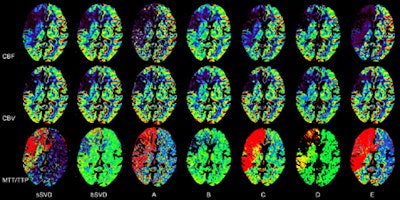

| Perfusion maps generated from identical source data by using different software. Unenhanced CT images (above) and perfusion maps (below) in 73-year-old man with right middle cerebral artery occlusion. CBF, CBV, and MTT/TTP maps generated with all software and by using sSVD and bSVD methods are displayed with same color lookup table, automatic color scale determination, and vascular pixel elimination. On unenhanced scan at admission (above, left), faint hypodense areas in right frontal operculum and basal ganglia are noted and final infarct area is identified on follow-up unenhanced scan (above, right). Decrease in CBF area measured with sSVD is much larger than that measured with bSVD, which is comparable with final infarct area. Software A, C, and E show almost same CBF changes as sSVD, while software B and D show almost same changes as bSVD. Abnormal MTT/TTP areas in sSVD and software A, C, D, and E were apparently larger than those in bSVD, software B, and final infarct area. Note that an erroneous MTT/TTP decrease in software A, B, D, and bSVD is seen in area of significant CBV decrease. Areas with CBV decrease are almost the same among all software. All images republished with permission of the Radiological Society of North America from Radiology, January 2010, Vol. 254:1, pp. 200-209. |